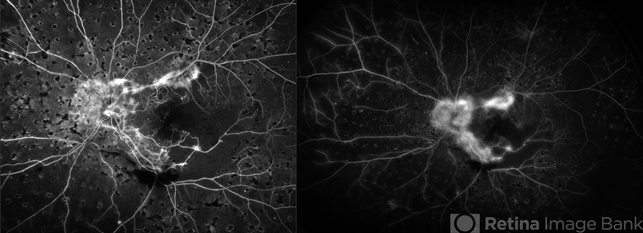

- proliferative diabetic retinopathy (PDR), diabetes, left eye, ischemia, fluorescein leakage, ultra-wide field imaging, Optos, neovascularization (NV), neovascularization of the disc (NVD)

- Ultra-wide field fluorescein angiogram of a patient with proliferative diabetic retinopathy affecting the left eye.